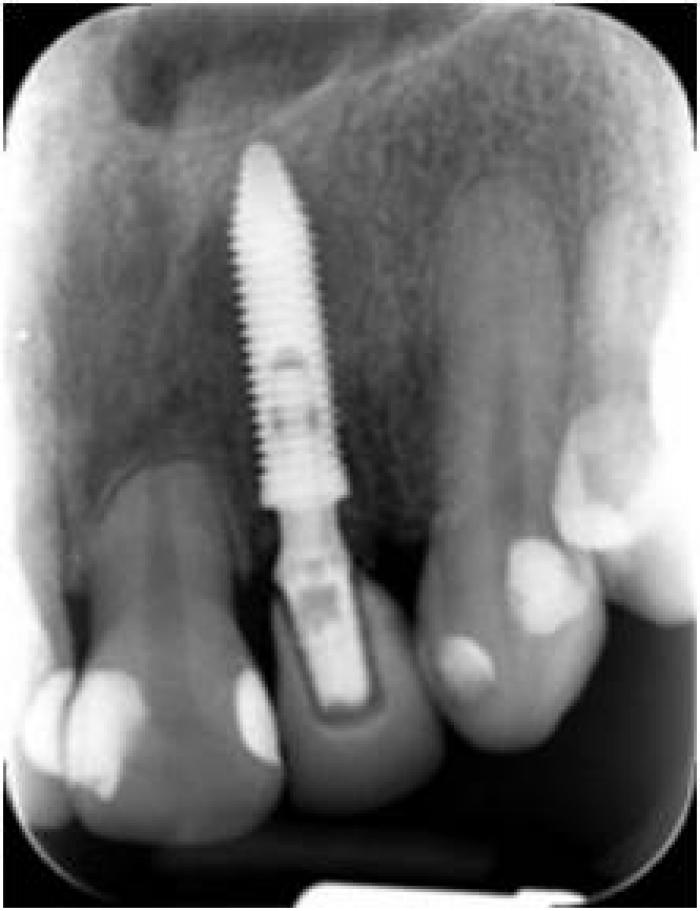

Raio x após extração do dente 22 por fratura de raiz, e instalação do implante Cone Morse - Clínica Cliniface

Raio x após extração do dente 22 por fratura de raiz, e instalação do implante Cone Morse